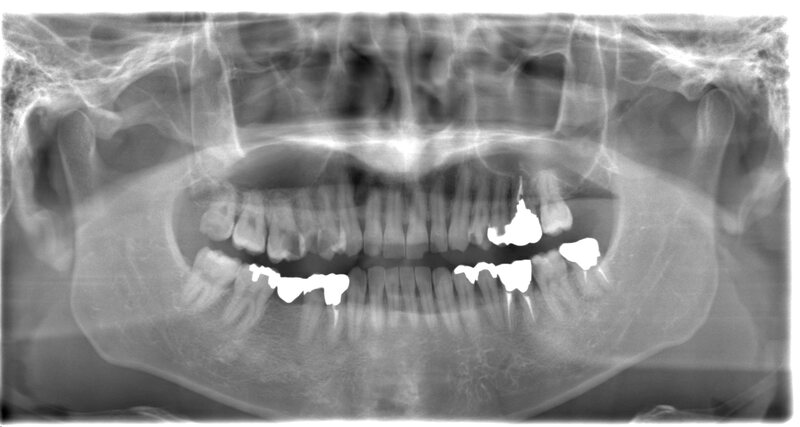

- お口全体のレントゲン撮影し確認します。

- 親知らずの形の確認と神経との位置を把握し安全に抜歯するため三次元のCTを撮影します。

CASE 2

抜歯前

抜歯後

基本情報

| 年齢・性別 | 20代・女性 |

|---|---|

| 主訴 | 左上の親知らずが抜きたい 左上8番 |

| 治療内容 | 通常抜歯 |

| 治療期間 | 約15分 |

| 治療費 | 約3,000円 |

| リスク・副作用 | 2〜3日は腫れと痛みがある。 |

CASE 3

抜歯前

抜歯後

基本情報

| 年齢・性別 | 30代・女性 |

|---|---|

| 主訴 | 右下の親知らずが痛い 右下8 |

| 治療内容 | 通常抜歯 |

| 治療期間 | 約15分 |

| 治療費 | 約3,000円 |

| リスク・副作用 | 2〜3日は腫れと痛みがある。 |